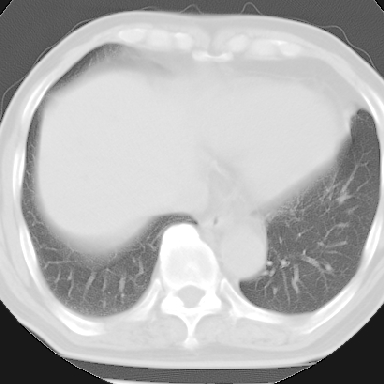

标题: CT8275:M 77 反复咳嗽咳痰10多年,慢性支气管炎请分析 [打印本页]

标题: CT8275:M 77 反复咳嗽咳痰10多年,慢性支气管炎请分析

m 77 反复咳嗽咳痰10多年,再发加重4天

纵隔窗呢?慢支炎肺气肿;余未见明显渗出及占位!

慢性支气管炎、肺气肿。

这份病例诊断慢支并气肿可能属过诊,首先慢支的临床诊断标准是严格的,应该弄清楚,其次ct表现是否符合该病表现,本例老年人ct肺窗表现应属正常,不要跟着临床跑。